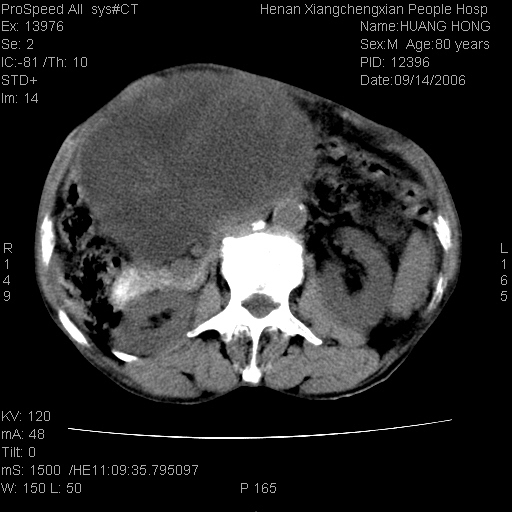

患者, 男, 80岁, 发现上腹部包块1年余,无其它不适.2006-9-14ct片是喝水后扫描2006-9-15ct片没喝水扫描![]() ![]() ![]() ![]() ![]() ![]() ![]() ![]() ![]() ![]() ![]() ![]() ![]() ![]() ![]() ![]() 以上是喝水片 以下是空腹片 ![]() ![]() ![]() ![]() ![]() ![]() ![]() ![]() ![]() ![]() ![]() ![]() ct:胰腺前方、肝脏与胃之间可见巨大类圆形囊性低密度影,大小约152mmx145mmx118mm,上缘平t11椎体上缘,下缘平l3椎体下缘,密度均匀,ct值15hu,其内呈多房分隔,囊壁薄且光滑,边界清晰,周围组织及器官明显受压。肝脏实质内未见异常密度影,胆囊未见异常,胰腺密度未见异常,脾脏大小、形态及密度未见异常,腹膜后间隙未见肿大淋巴结影。 印象:胰腺前方、肝脏与胃之间巨大类圆形囊性低密度影.性质待定。多考虑:.肠系膜巨大囊肿。 守望可可西里发言:支持楼主,考虑肠系膜囊肿,多为小肠系膜。 ysxyy发言:我总觉得这个病人虽然很像肠系膜囊肿,但还是应该强化一下; 下面这几幅图里肿块和主动脉的关系不太清,不知能否除外血管性来源? ![]() ![]() ![]() 病理结果:横结肠系膜间叶瘤.部分区域间质细胞增生活跃. 病理图片 ![]() 良性间叶瘤:是指由两种或两种以上的间叶组织所构成的混合性肿瘤.肿瘤仅发生在腹膜后和肠系膜,.前者较后者多发.良性间叶瘤常发生在肾或四肢,腹膜后较少见,各年龄均可发病.女多与男,预后较好,但术后易复法. 恶性间叶瘤:由两种以上恶性间叶组织成分组成. 光镜:肿瘤由脂肪/血管/平滑肌构成. 原贴地址: http://www.radinet.com.cn/forum_view.asp?forum_id=4&view_id=16217 ok |